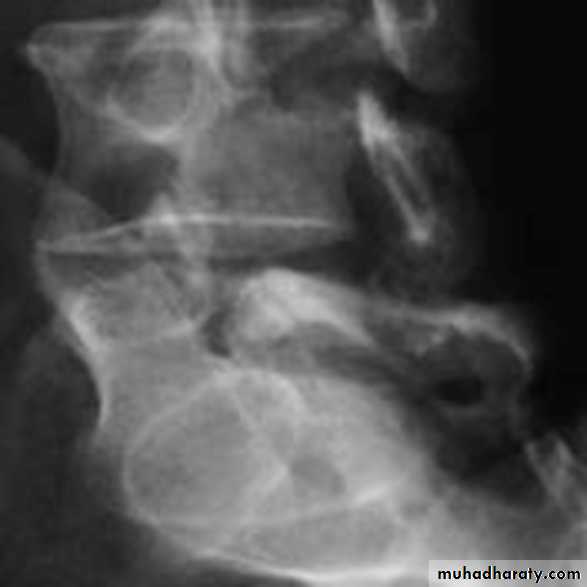

Spondylolysis and spondylolisthesis

Spondylolisthesis: is a term denoting fore ward or backward movement of a vertebra relative to the vertebral segment below, typically due to spondylolysis (pars interarticularis defects) .Spondylolysis: Spondylolysis is a defect in the pars interarticularis of the neural arch, the portion of the neural arch that connects the superior and inferior articular facet in which cause defect in the neck of scotty dog .

scotty dog sign refers to the normal appearance of the lumbar spine when seen on oblique radiographic projection. On oblique views, the posterior elements of vertebra form the figure of a Scotty dog with:

the transverse process being the nose

the pedicle forming the eye

the inferior articular facet being the front leg

the superior articular facet representing the ear

the pars interarticularis (the portion of the lamina that lies between the facets) equivalent to the neck of the dog.